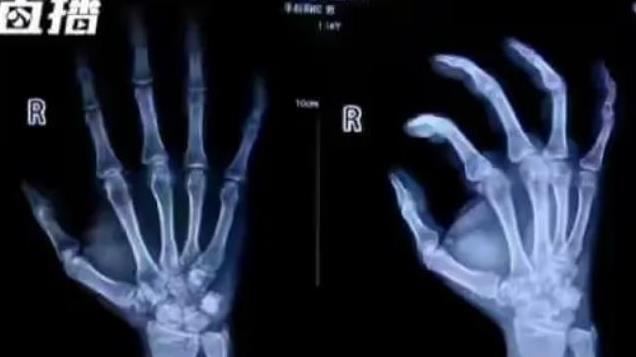

中國發生一起荒謬事件,湖北一名男子車禍後稱小拇指骨折,向對方索賠1萬元人民幣(換算約新台幣4.5萬元)。結果在對方報警後,警方懷疑男子骨折為舊傷,一查之後發現,男子的小拇指一個多月中,已經以車禍骨折為由超過30次,獲賠約20萬人民幣(換算約新台幣90萬元)。

據《網易新聞》報導,中國湖北一輛轎車突然轉向,導致電動車三輪車撞上一旁騎腳踏車的黃姓男子,黃姓男子聲稱小拇指骨折,索賠1萬元,而電動車騎士決定報警處理。警方調查後發現,一個多月中黃姓男子的小拇指骨折30多次,懷疑黃姓男子是詐騙集團。

另外,為了使傷勢逼真,常常跟同夥一起弄斷小拇指,方法是將手指用紗布包裹,並使用鐵槌用力將手指敲到骨折,一共30多次,目前黃男以及駕駛轎車的同夥都已經被拘留。